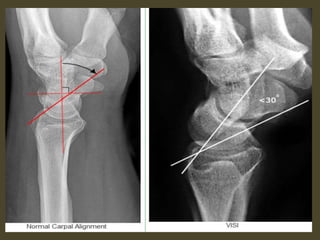

A simple approach is to consider the lunate

which is usually the easiest carpal bone to

visualize on a lateral wrist image. If the

lunate is abnormally tilted in a dorsal

direction on a standard lateral wrist image,

a DISI should be considered. If the lunate is

abnormally tilted in a volar direction a VISI

should be considered. DISI is due to

disruption of the scapho-lunate articulation.

VISI is secondary to disruption of the luno-

triquetral articulation.

DISI deformity.

DISI.

Volar intercalated segmental instability(VISI).

VISI with volar tilting of the lunate.

VISI with luno-triquetrum ligament tear and volar tilting of the lunate.

VISI deformity secondary to Lunotriquetral ligament tear.